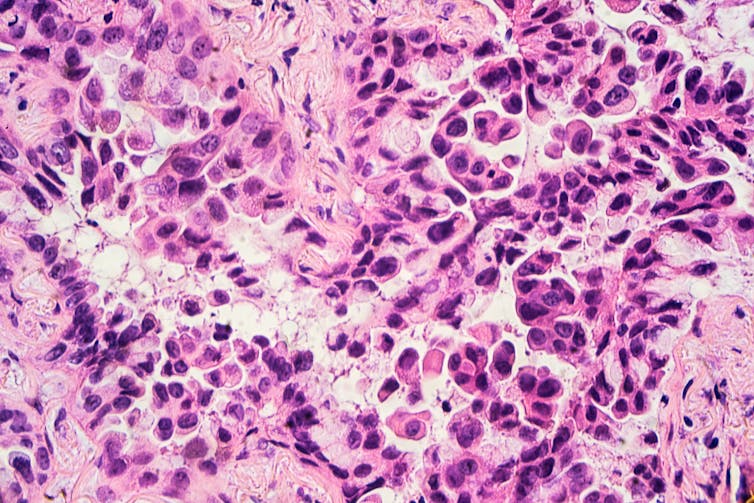

Like any cancer, lung cancer consists of abnormal cells that proliferate in an uncontrolled fashion, do not obey normal signals to die and cannot repair their DNA. Normal lung cells become cancerous through exposure to tobacco smoke, radon gas, asbestos or airborne pollutants.